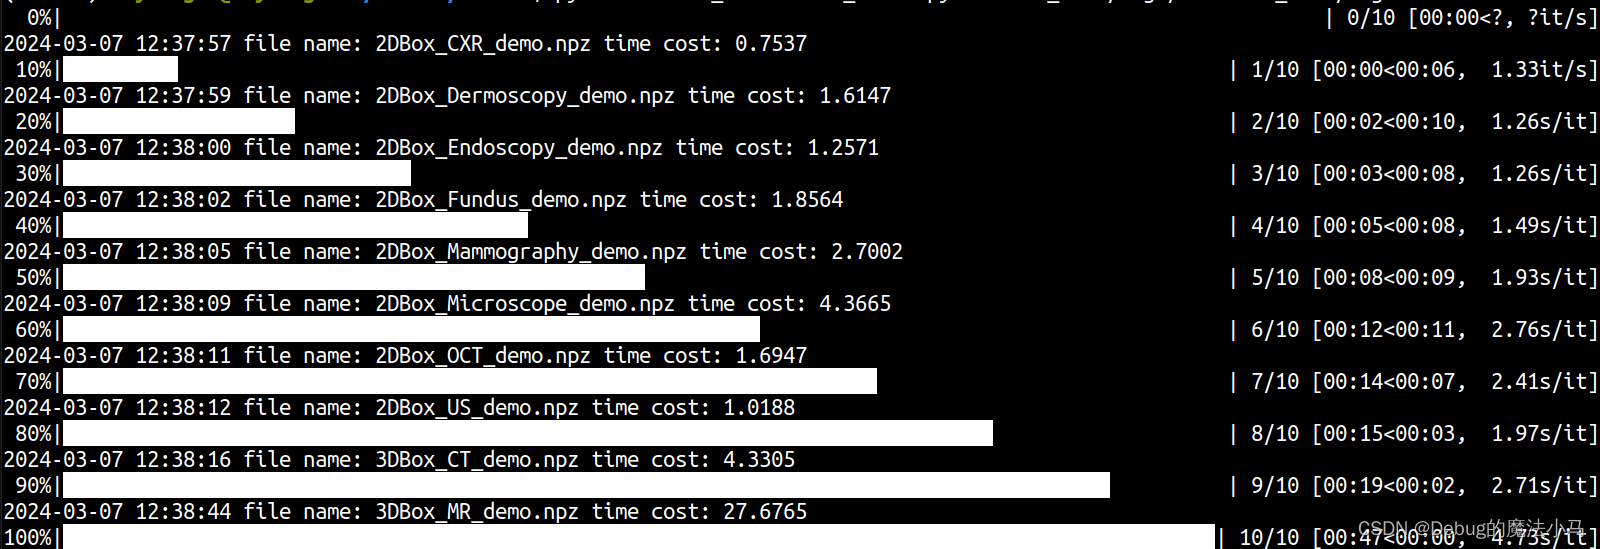

成功: